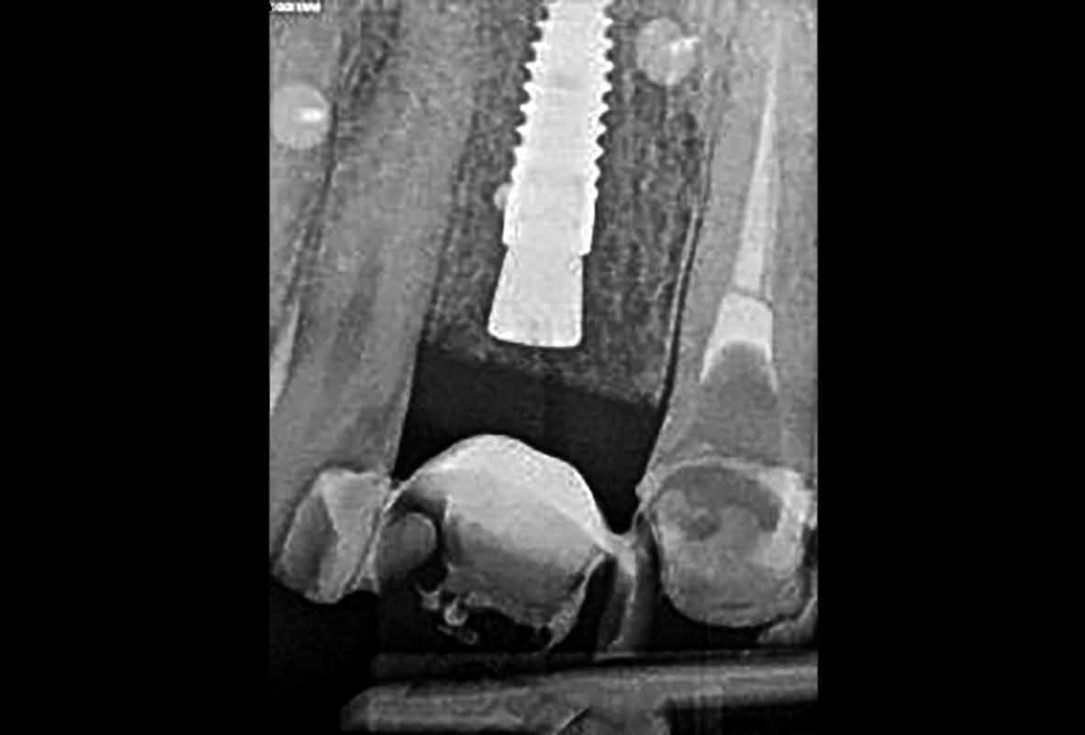

Full maxillary reconstruction with maxgraft® bonebuilder - Dr. C. Hilscher

Initial x-ray, ten years post implantationem alio loco, large peri-implant bone loss